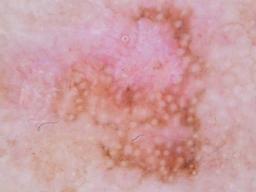

{

"age_approx": 60,

"anatom_site_general": "upper extremity",

"concomitant_biopsy": false,

"diagnosis_1": "Benign",

"diagnosis_2": "Benign melanocytic proliferations",

"diagnosis_3": "Nevus",

"diagnosis_confirm_type": "serial imaging showing no change",

"image_type": "dermoscopic",

"lesion_id": "IL_6731115",

"melanocytic": true,

"sex": "male"